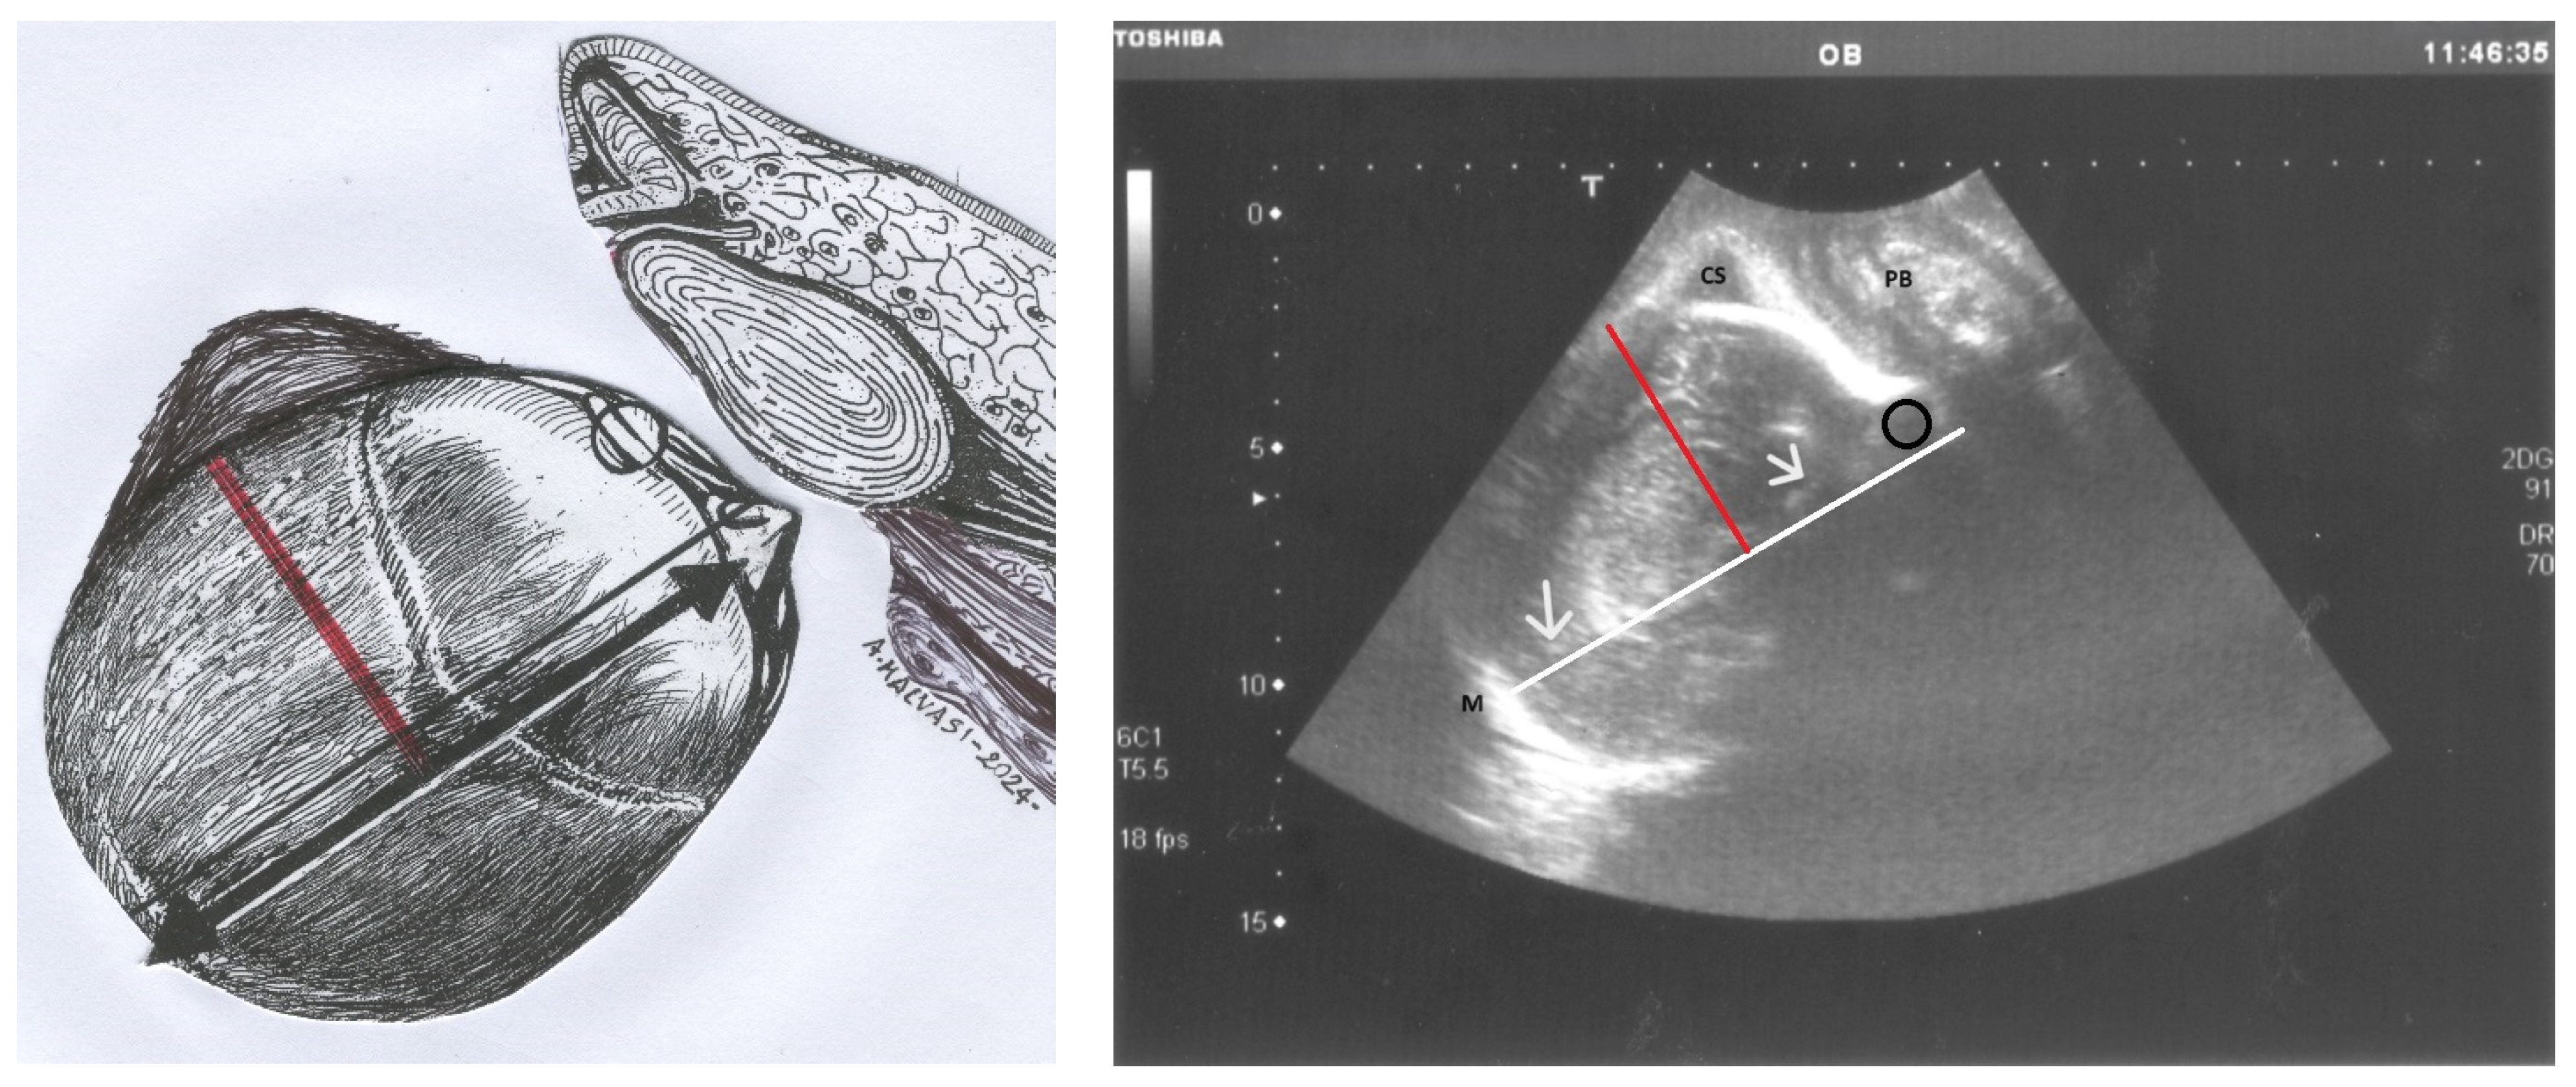

- Malvasi, A.; Tinelli, A. Intrapartum sonography: Two sings to detect asynclitism degree. J. Matern. Neonatal Med. 2016, 29, 1289–1290. [Google Scholar] [CrossRef]

- Birol Ilter, P.; Yassa, M.; Timur, H.; Dogan, O.; Tekin, A.B.; Haydar, A.; Gulumser, C.; Tug, N.; Malvasi, A.; Tinelli, A. Intrapartum ultrasound for fetal head asynclitism: Is it possible to establish a degree of asynclitism to correlate to delivery outcome? Int. J. Gynecol. Obstet. 2023, 163, 271–276. [Google Scholar] [CrossRef]